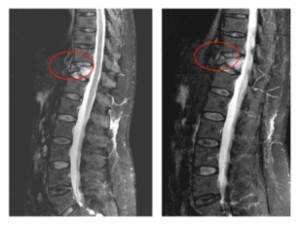

Comparación pre- y post-operatoria de una cifopastia cementada

Mujer, edad 55 años, Fractura aplastamiento derecho de L2

Antes 1

Después 1

Antes 2

Después 2